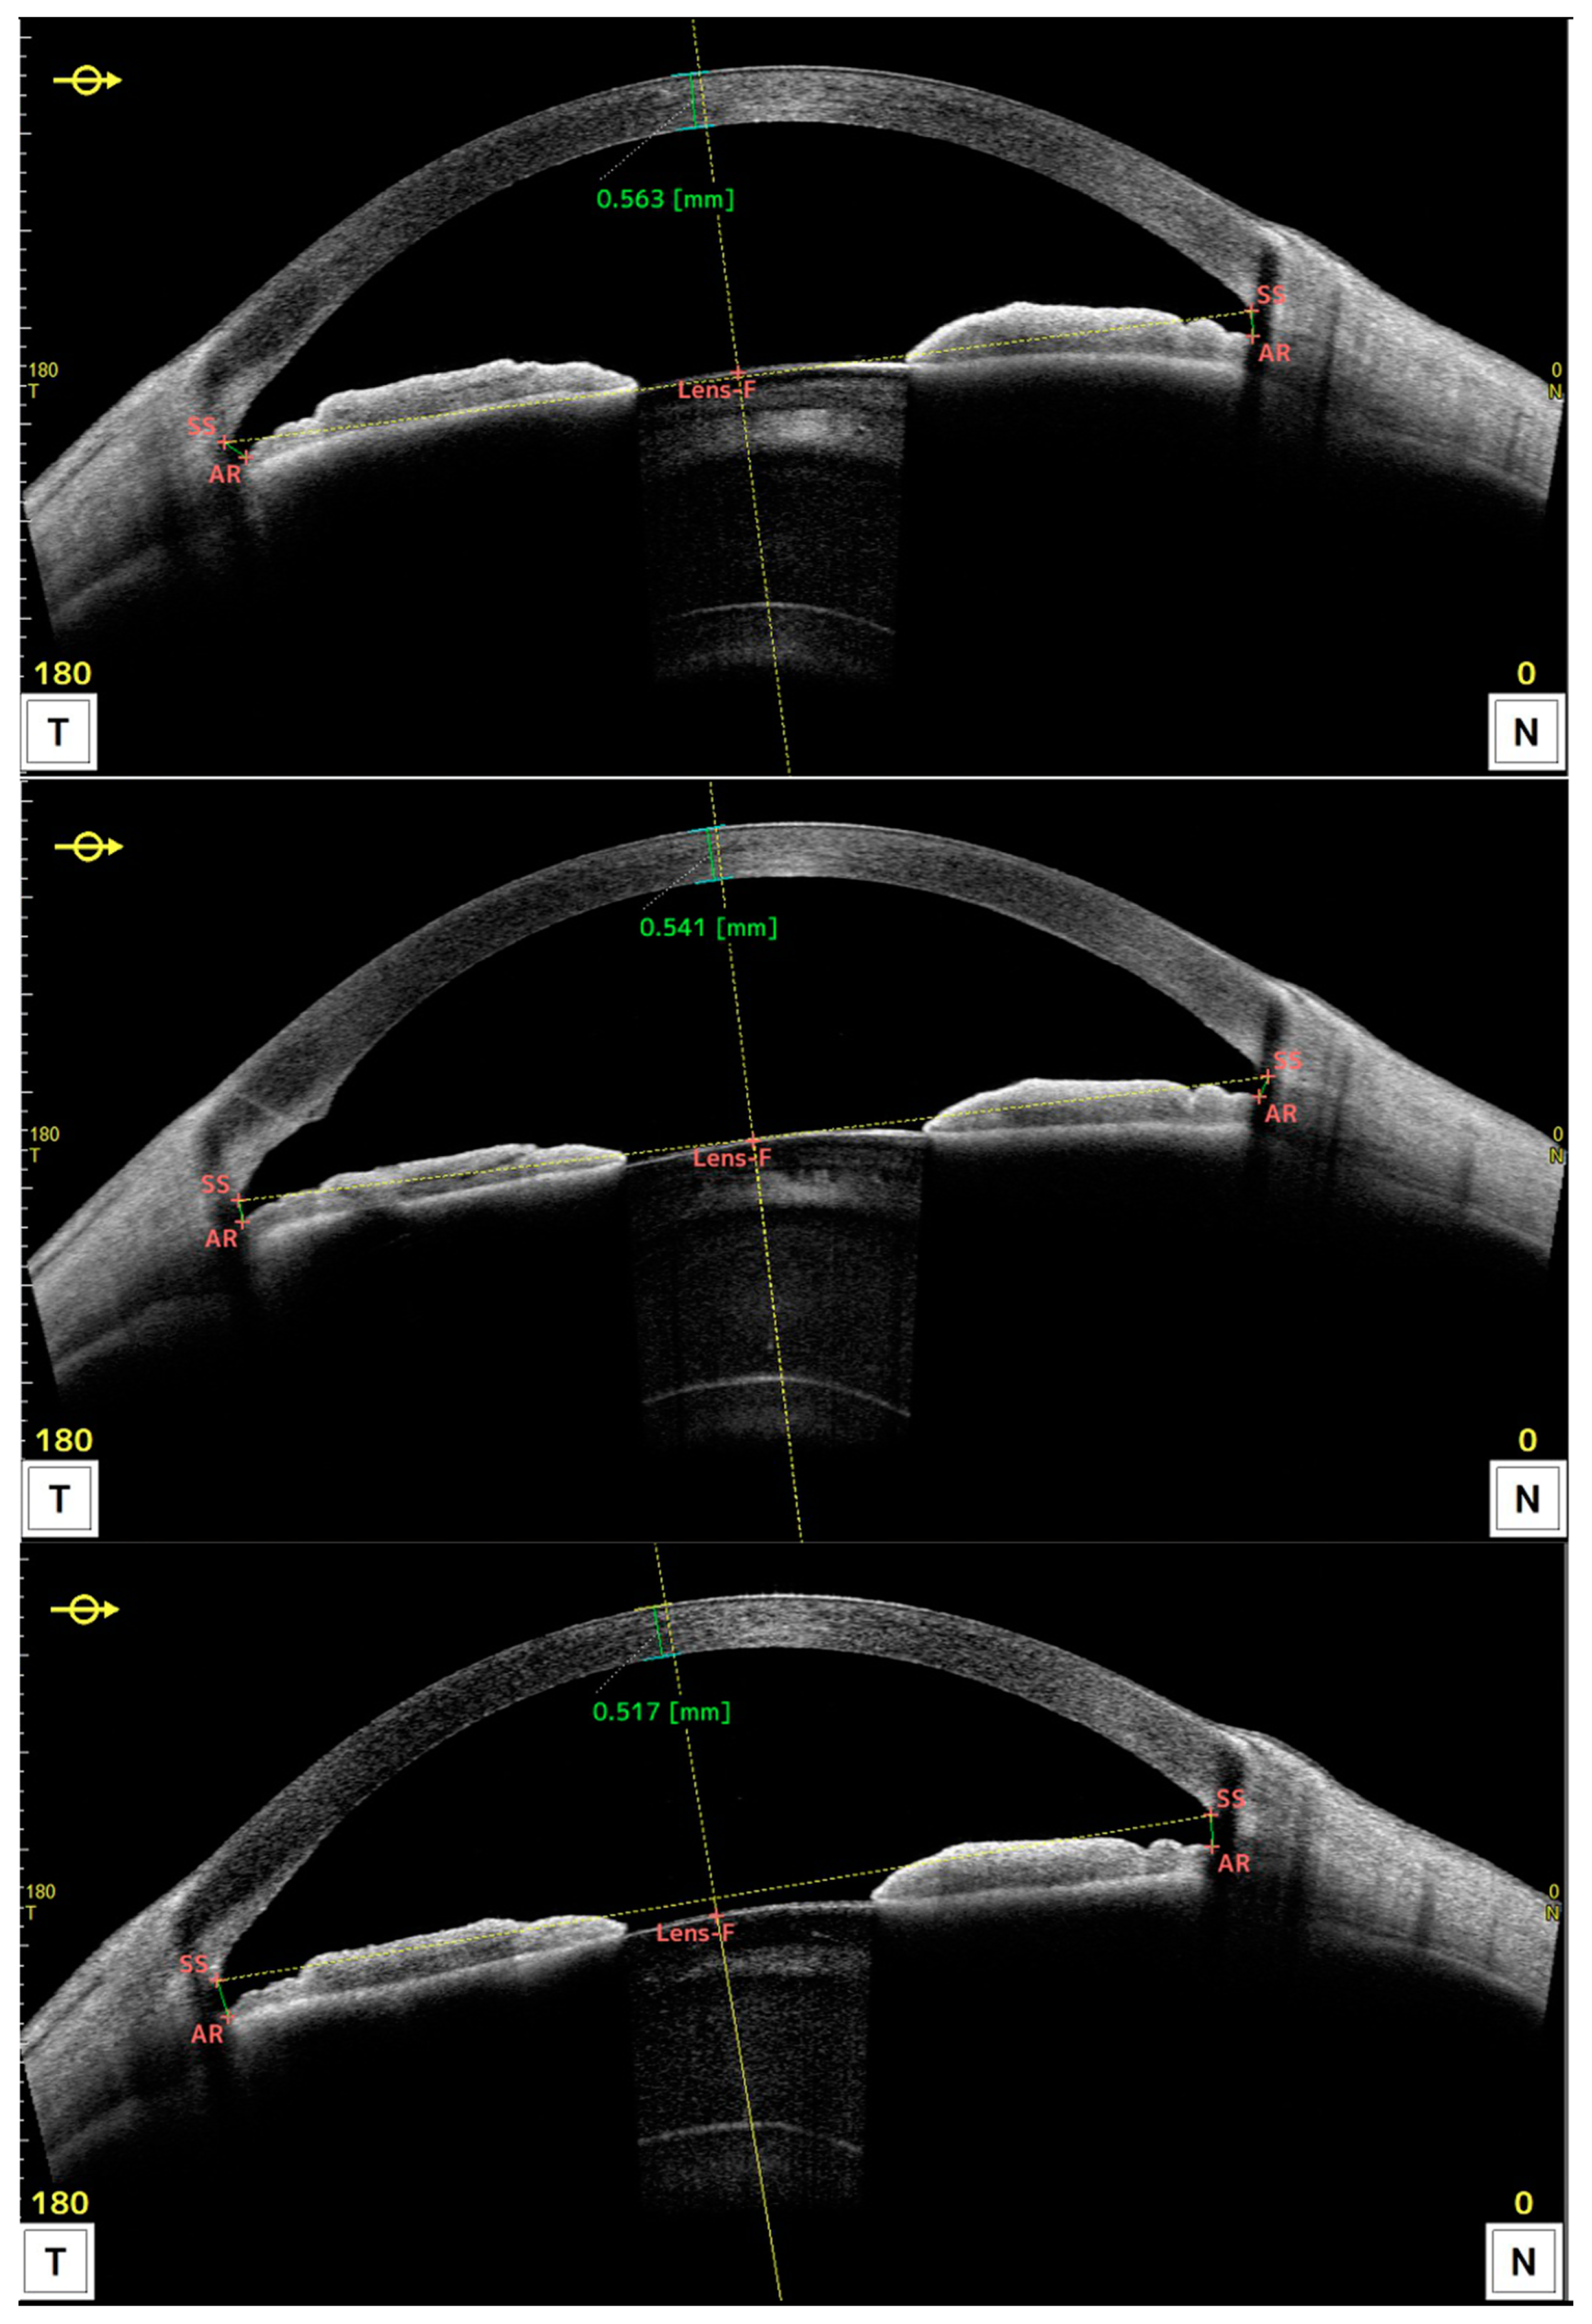

4. DSO Cases